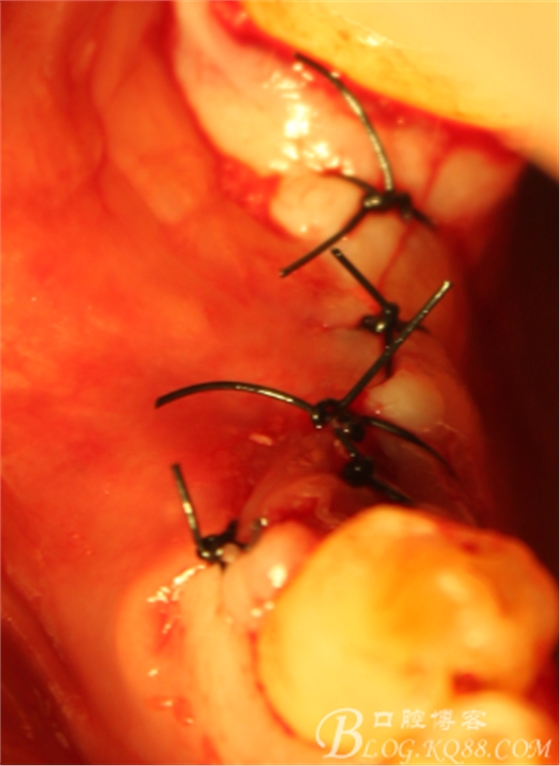

上愈合基臺(tái),間斷縫合關(guān)閉創(chuàng)口,頰側(cè)牙齦部分恢復(fù)形態(tài)

2周閉口式模型轉(zhuǎn)移

一月復(fù)查,上皮袖口封閉良好,牙齦恢復(fù)正常外形凸度,但近中齦乳頭仍不理想